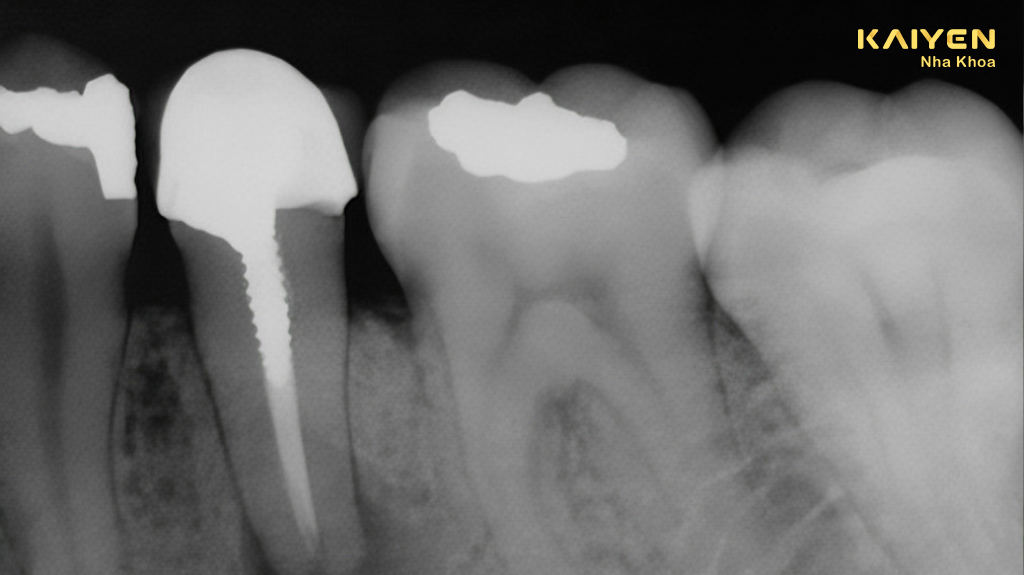

Cắm chốt răng hay còn gọi là cắm chốt tủy, đây là phương pháp mà bác sĩ sẽ đặt một chốt hình trụ dài vào ống tủy chân răng để giúp giữ cùi răng. Thông qua chốt này, phần cùi răng và mô chân răng sẽ liên kết chặt với nhau, lúc truyền tải lực nhai xuống chân răng một cách hiệu quả mà không bị nứt gãy.

Sau khi cắm chốt răng, bác sĩ sẽ tiến hành tái tạo lại phần cùi răng bằng cách bổ sung các vật liệu như composite, ionomer thủy tinh xung quanh rồi sau đó bọc mão sứ lên trên. Việc cắm chốt răng chỉ được chỉ định trong trường hợp răng đã điều trị tủy và cho kết quả tốt, vì bản chất của chốt răng là cắm vào tủy, nên trường hợp chưa điều trị tủy hoặc điều trị thất bại thì không thể chỉ định được.

Lần hẹn thứ nhất: Bác sĩ sẽ khoan rộng ống tủy, lựa chọn chốt phù hợp với chiều dài và đường kính của ống tủy đã khoan rồi thực hiện gắn bằng cement đặc hiệu. Sau đó bác sĩ sẽ thực hiện trám tái tạo cùi răng bên trên với vật liệu trám vĩnh viễn sau đó thực hiện việc lấy khuôn răng.

- Kích thước chốt thích hợp với hình dạng của ống tủy chân răng.

- Chốt phải vừa vặn và lớp trám bít phải kín.